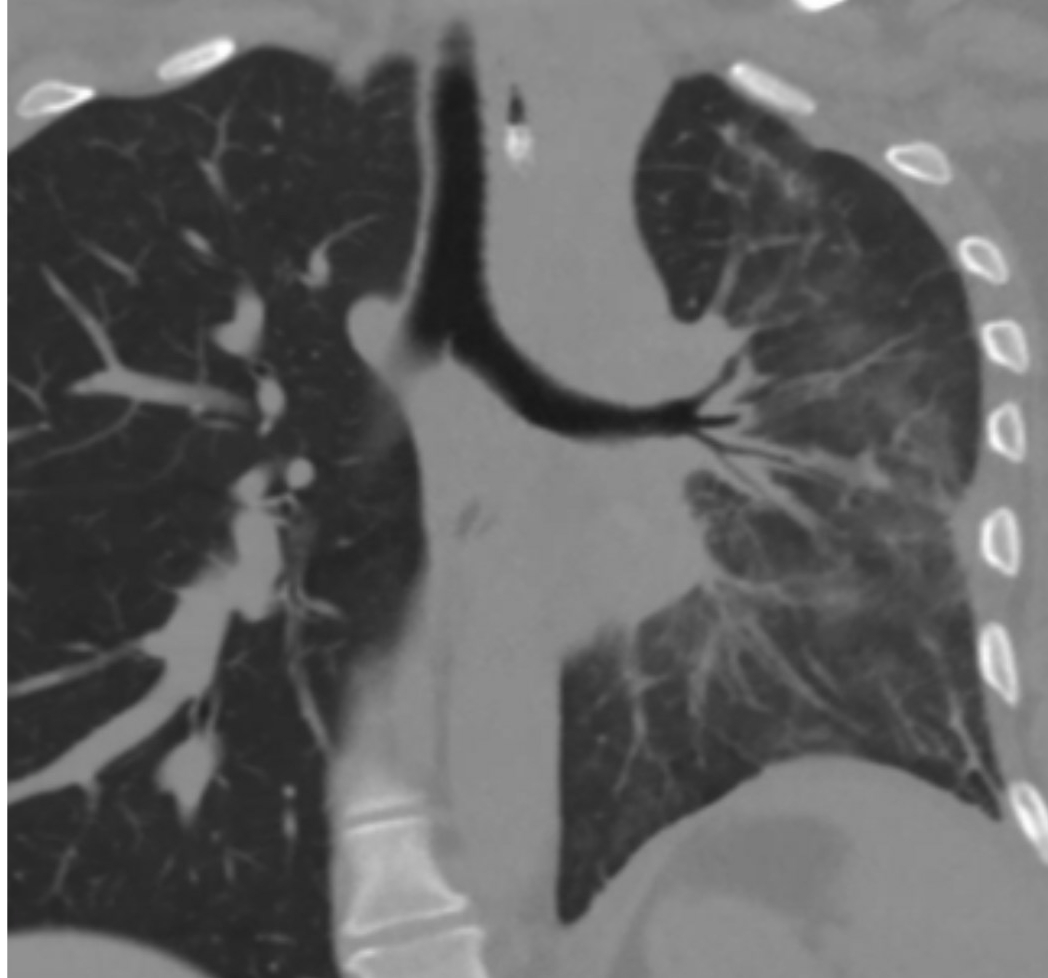

A 37-year-old G1P1 female with known idiopathic FM and a previous mediastinectomy presented at 23 weeks and 3 days with preterm labor and cervical dilation to 4 cm. She received steroids and magnesium for fetal neuroprotection. In the days prior to delivery, she experienced hemoptysis, prompting pulmonology consultation. She was managed conservatively with chest physiotherapy and nebulizers. The patient had no more hemoptysis and at 24 weeks and 1 day, she underwent classical cesarean delivery for breech presentation and non-reassuring fetal heart tones. The neonate was admitted to NICU and the patient was discharged in stable condition. Outpatient imaging revealed a stable calcified mediastinal mass causing 80% narrowing of the left main bronchus and left lung atelectasis. Subsequent bronchoscopy with balloon dilation improved airway patency, but stenting was deferred.

FM can remain stable during pregnancy, but physiologic changes in pregnancy such as increases in blood volume and cardiac output can be exacerbated by FM, potentially leading to pulmonary hypertension and reduced blood flow to the uterus. Notably, FM-related airway obstruction may not always present with overt respiratory distress and can be managed conservatively in select patients. Also, while balloon dilation may offer symptomatic relief, stenting decisions must be individualized based on functional status and patient preference. Finally, early multidisciplinary collaboration is crucial to prepare for peripartum respiratory complications in patients with known mediastinal pathology.